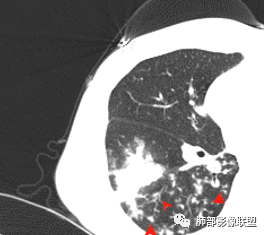

患者青年女性咳嗽、咳痰1月,加重1周,发热3天。患者1月前受凉后出现咳嗽,咳少量白色痰,1周前咳嗽加重,痰量增多,为黄白色黏痰,偶有痰中带血,轻微胸闷,近3天来出现发热,最高体温38.4℃,伴乏力,食欲下降。辅助检查:血常规白细胞及中性分类 血沉 CRP均增高。胸CT:右肺下叶前基底段实变病灶内可见空洞,洞内可见气液平面,病灶周围及右肺下叶背段可见树芽征 、结节。经抗感染治疗,基底段病灶较前缩小,背段病灶 融合 增大。考虑良性病变,空洞性肺结核合并细菌感染。

29岁女性,既往体健。咳嗽咳痰(白黏痰)一月,加重一周(黄白痰),发热3天伴咯血。血常规:中性粒、CRP升高,血沉增高。CT:右肺下叶不规则厚壁空洞伴散在树芽、小叶中心结节。空洞内壁光滑,似见液平。无胸腔积液及明显纵膈肿大淋巴结。予左氧及美洛西林舒巴坦治疗12天,临床症状减轻。复查CT见空洞明显吸收缩小,增强见薄壁空洞,内有液平,引流支气管增厚。考虑感染;是单纯细菌感染还是结核感染?还是细菌合并结核?建议痰找抗酸杆菌,痰培养,并继续复查肺部CT,可完善支气管镜检查。

青年女性,有低热,咳嗽,白细胞稍高,血沉高,右下叶背段可见不规则形厚壁空洞,内壁光整,周围见小花小草样斑片簇状影分布,右下叶背段支气管增厚,似有空洞相连,抗感染性治疗后,右下叶斑片影较前部分吸收减少,右下叶背段空洞缩小,但周围斑片影较前进展,右下叶背段支气管壁增厚,变窄,常规考虑继发性肺结核可能,建议增强,支气管镜及痰检痰培,结核分枝杆菌检查。

抗感染治疗后短期复查右肺病灶变化明显,部分病灶如空洞性病灶明显吸收,部分病灶稍有增大融合(如背段病灶)。

可以基本明确合并细菌感染,且变化部分不宜用结核感染解释。